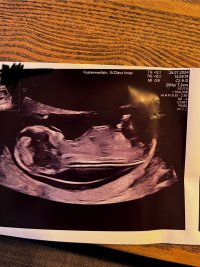

Så bra <3 fikk du vite kjønn?13+0 målt til 13+4Alt fint. Hematomet har minsket i størrelse heldigvis

UL bilder❤️

Har ikke sett så mange bilder som er direkte av «mellom beina» her inne. Sjekker de ikke det? Da kan f.eks. de «tre strekene» som kan indikere jente, være lettere å se.Ultralyd gikk kjempebra, ble satt frem fra 12+1 til 13+0Noen som kan gjette kjønn? Så ingenting som «stakk opp» mellom føttene

De ville ikke si noe så tidlig på St. Olavs, sa at så tidlig ser det likt utHar ikke sett så mange bilder som er direkte av «mellom beina» her inne. Sjekker de ikke det? Da kan f.eks. de «tre strekene» som kan indikere jente, være lettere å se.

Jeg ville sagt gutt!Vår lille, 13 + 0!

Nub gruppen på Facebook sier jente. Jeg klarer ikke tro på det. Legen som tok TUL ble sur og ville ikke si noe om kjønn..

Fikk vite 99% jente av nub eksperter

Ser ut som jente jaVår lille, 13 + 0!

Nub gruppen på Facebook sier jente. Jeg klarer ikke tro på det. Legen som tok TUL ble sur og ville ikke si noe om kjønn..

Fikk vite 99% jente av nub eksperter

Tre gutter, så tør jo nesten ikke håpeSer ut som jente ja

Jeg tipper også jenteVår lille, 13 + 0!

Nub gruppen på Facebook sier jente. Jeg klarer ikke tro på det. Legen som tok TUL ble sur og ville ikke si noe om kjønn..